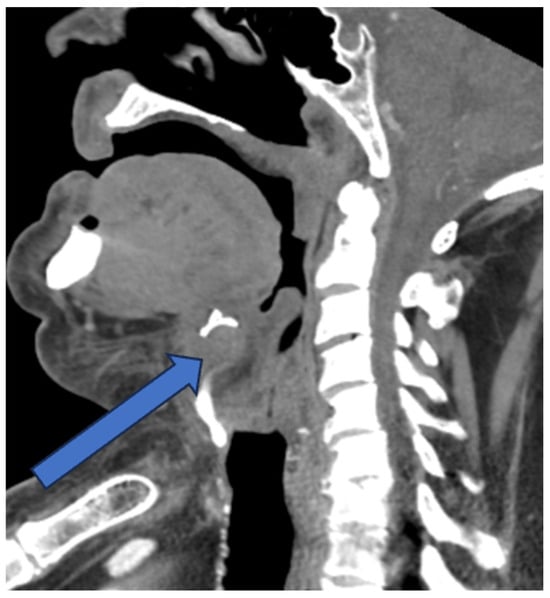

A 74-year-old man presented to the Emergency Department with a two-day history of swelling and erythema of the anterior cervical area without fever, spontaneous pain or cervical tightness. However, odynophagia was present with minor right dominant pain on palpation of the thyrohyoid complex. The personal history revealed diverticulosis, an active smoker of 50 pack years and no current medication. On physical examination the patient presented with an erythematous and warm swelling extending over an area of 7 × 7 cm from submental to the thyroidal cartilage with minimal right dominance (Figure 1). The remaining ENT examination including flexible nasal laryngoscopy was unremarkable. The blood work showed elevated inflammatory parameters (Lc 6 G/L, CRP 80 mg/L). On ultrasound of the neck, hyperechogenic swelling of the soft tissues in the anterior cervical region (Levels Ia and VI) with ill-defined borders and singular hypoechogenic foci were visible. A computed tomography (CT) scan of the neck showed a median anterior cervical right-dominant thyro-hyoidal lesion with discrete radiocontrast enhancement along the thyrohyoid membrane and the hyoid bone with peripheral tissue inflammation but no abscess (Figure 2).

Figure 2. Sagittal view on a CT scan showing unspecific inflammatory lesion of the soft tissue. Arrow pointing to the thyrohyoid membrane and the hyoid bone with peripheral tissue inflammation.

Our patient presented in a rare acute manner with slight induration, tenderness and erythematous skin with ill-defined borders at the antero-lateral neck region. This prompted the administration of an empiric antibiotic treatment and performance of an ultrasound and CT scan to rule out a deep neck infection. However, there are no specific diagnostic radiologic findings in the diagnosis of the thyrohyoid syndrome [1]. We concluded that our patient additionally exhibited subcutaneous inflammation, possibly due to secondary local infection, but clearly showed the pathognomonic point of acute tenderness over the greater horn of the hyoid bone. A possible origin of the inflammation is believed to be subsequent to placing stress on the connective tissues by voice abuse, swallowing, chronic cough, neck and upper limb overuse or cervical trauma [5]. A history of antero-lateral or lateral neck pain, odynophagia and foreign body sensation confirms the diagnosis along with finger or thumb pressure to find the pathognomonic point of acute tenderness over the greater horn of the hyoid bone and sometimes also the upper border of the thyroid cartilage.